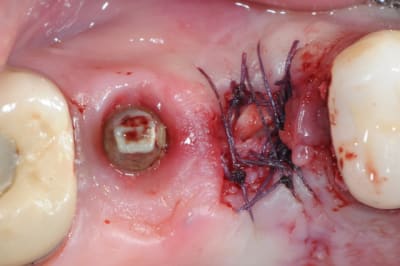

ton intervention, albert, me rappel un cas clinique que j'aimerai partager avec vous:

1-2-3 prémolaire foutu juste à proximité d'un implant, faut donc faire gaffe aux tissus environnant.

en plus je suis sure que la corticale vestibulaire est K.O elle aussi.

4-5: eh ben oui, elle est détruite! une simple curette insérée dans l'alvéole permet de visualiser l'importance de la perte osseuse vestibulaire.

que faire ??